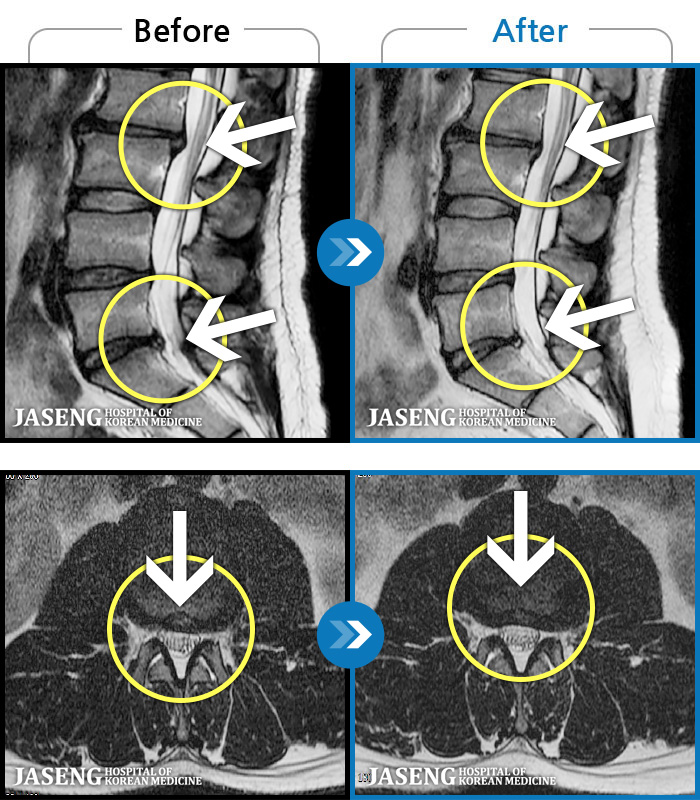

허리디스크

인천 · 강아현 원장

물건을 들다 삐끗한 후 발생한 허리 통증 및 하지 방사통, 하지 감각 저하 및 근력 저하 발생

촬영시기

2025.03.04 ~ 2025.09.10

2025.09.22

조회수 248